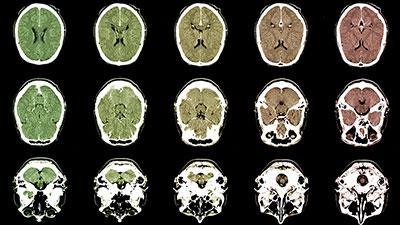

Brain imaging and function

This project is to develop MR brain imaging techniques to study brain characteristics and functions. Ida Pu with Royal Academy of Engineering Travel.

• Ida Pu et al, 'Gray matter nulled and vascular space occupancy dependent fMRI response to visual stimulation during hypoxic hypoxia', NeuroImage 59(4): 3450-3456 (2012)

• Ida Pu et al, 'Quantification of venous vessel size in human brain in response to hypercapnia and hyperoxia using magnetic resonance imaging', Magnetic Resonance in Medicine Volume 69, Issue 6, pages 1541–1552, June 2013

• Ida Pu et al, 'Efficient algorithms for noise propagation in diffusion tensor imaging', in London Algorithmics 2008: Theory and Practice: (Texts in Algorithmics) eds. J Chan, J K Daykin, M S Rahman, 1 June 2009, ISBN: 978-1904987970